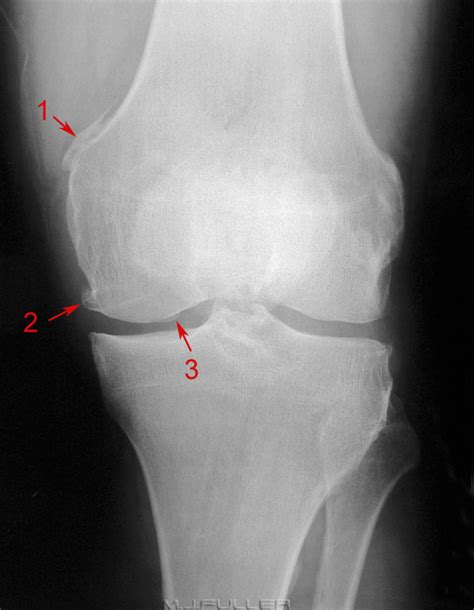

Pellegrini Stieda / The Pellegrini-Stieda lesion. Ossification along the ... : There is a moderately large knee effusion.

This occurs due to the deposition of calcium on the inner side of the knee. Pain and restriction of movements. Most of the cases of pellegrini stieda lesions are not symptomatic, and pellegrini stieda syndrome is said to exist when the lesion becomes symptomatic i.e. Is the presence of a radiological finding of calcification on the medial side of the knee as a consequence. The diagnosis pellegrini stieda disease was made.

It is a common incidental finding on knee radiographs. Most of the cases of pellegrini stieda lesions are not symptomatic, and pellegrini stieda syndrome is said to exist when the lesion becomes symptomatic i.e. Pain and restriction of movements. Learn about this soft tissue calcification around the knee joint. Is the presence of a radiological finding of calcification on the medial side of the knee as a consequence. There is evidence of osteoarthritis. Pellegrini stieda syndrome is a medical problem which is characterized by pain, swelling and inflammation in the knee. #foamed #foamrad #radiology #rad #elearnrad #voxelz #varunbabu #drbabu. Ayurvedic treatment is the natural way to treat pellegrini stieda syndrome. The cause of the knee effusion is unknown. There is a moderately large knee effusion. This occurs due to the deposition of calcium on the inner side of the knee. It is likely that this patient has been an active sportsman in the past.